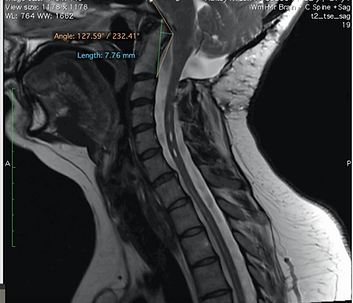

The following measurements are frequently used to assess both instability and the degree of brainstem compression. As with imaging, there is no consensus on which angles are the best to use to allow for diagnosis.

Clivo Axial Angle (CXA) - A line along the clivus and a second one down on the posterior side of the axis. (Abnormal: <150 degrees in flexion and 180 degrees in extension) This angle alone can does NOT equal a diagnosis of CCI

Grabb-Oakes - To diagnose brainstem compression. A line on middle sagittal MRI scans from the lowest point of the clivus to the lowest posterior point of the axis corpus. Measure in a right angle from this line to the beginning of the spinal canal. (Pathological: > 8 mm)

Clivio-Axial Angle Example

Mouse Roll Over: This is an example of areas used for measuring, not a tool to be used for accurate measuring